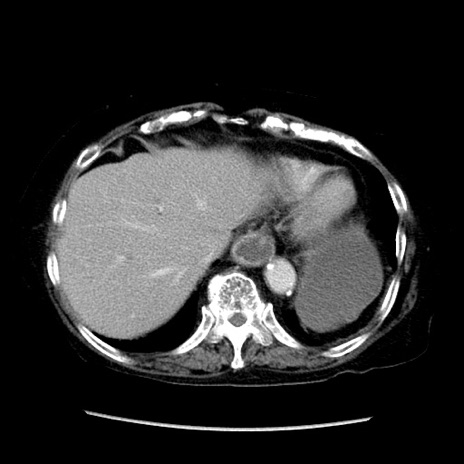

冠状断像

【症例】 90歳代女性

【主訴】 腹痛・嘔吐

【現病歴】今朝から左側腹部痛を認めた。 経過観察していたが、嘔吐を認めたため来院。

【既往歴】 子宮癌術後

【身体所見】 意識清明、BP 127/54mmHg、P 98bpm Sp02 95%(RA)、BT 35.8°C、腹部平坦・軟腸ぜん動音聴取良好、右下腹部圧痛(+) 反跳痛なし

【データ】WBC 9800、CRP 0.46